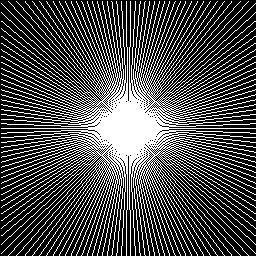

As shows in Fig. 1, at the first several iterations, the loss of is slightly larger than that of . Because the input is corrupted with severe artifacts, thus the role of data-driven module is significant at the first several steps. But as process goes on, repeated denoising operation in turn causes over-smoothing. While module can make up for it by incorporating model based knowledge. Though can improve the performance, it cannot ideally converge to a desired solution. The solid line indicates the superiority of Ours over other choices in both convergence rate and reconstruction accuracy. The execution time of , , and Ours is 4.4762s, 3.3240s, 6.2760s and 2.5225s, respectively. As expect, the proposed method provides a much faster reconstruction process. Thus we can verify that our framework has higher efficiency both in terms of theoretical convergence and practical execution time. The visualized results in Fig. 2 also verify that Ours has better performance than others.

In experiments we include three common used types of undersampling masks such as the Cartesian pattern in (?), Radial pattern in (?) and Gaussian mask in (?). Fig.11 gives a visualization of the three kinds of patterns at a unified sampling ratio of 30%.

| Cartesian | Radial | Gaussian |